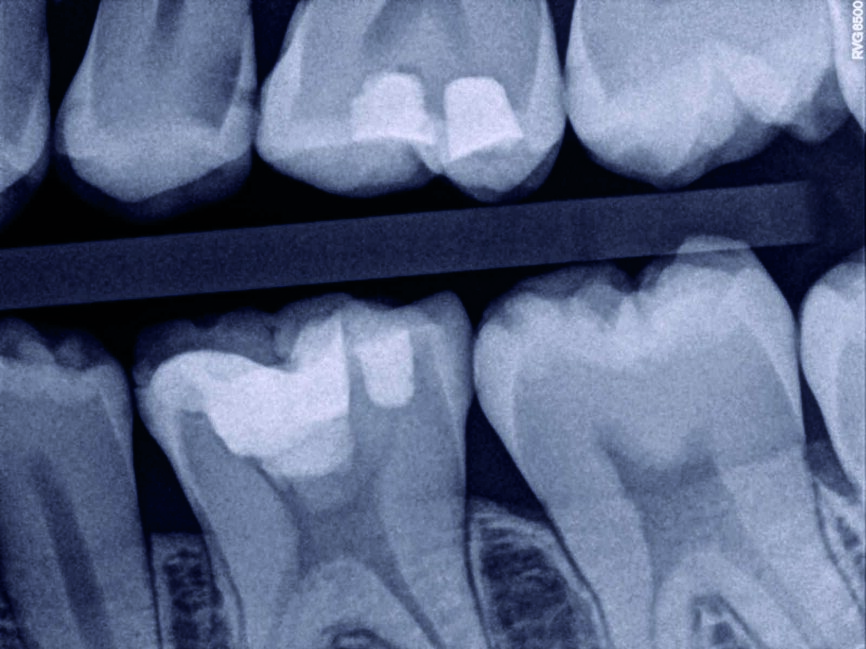

Ein 35-jähriger Patient kam mit vorübergehenden, provozierten Zahnschmerzen an Zahn #4 in die Zahnklinik. Die Diagnose lautete reversible Pulpitis. Es wurde dasselbe Behandlungsprotokoll zum Erhalt der Pulpenvitalität wie im klinischen Fall 1 eingehalten (Abb. 10, 11 und 12), nur dass in diesem Fall die endgültige Zahnreparatur nicht während derselben Sitzung erfolgte. Stattdessen wurde ein vorübergehendes strahlendurchlässiges Reparaturmaterial eingesetzt. Damit konnte die richtige Dicke des Materials für die Pulpa-Überkappung und seine korrekte Positionierung auf der Höhe des Lochs gewährleistet werden, während der Zahnrand für ein gutes Klebeprotokoll sauber gehalten wurde (Abb. 13, 14 und 15). Es wurde berichtet, dass die Erfolgsrate bei den Behandlungsverfahren zum Erhalt der Pulpenvitalität abfallen kann, wenn die endgültige Zahnreparatur zwei Tage nach dem ursprünglichen Verfahren durchgeführt wird. (8) Das MAP-System ist äußerst hilfreich im Hinblick auf eine präzise und stabile Platzierung des Überkappungsmaterials bei unmittelbaren und mittelbaren Verfahren sowie bei partiellen und vollständigen Pulpotomien. In diesem Fall erfolgte die abschliessende Reparatur 15 Tage nach dem ursprünglichen Verfahren und der Patient war vollständig symptomfrei. Neun Monate später wurde die vollständige Bildung des Kalkgewebes auf der Höhe der Pulpen-Überkappung festgestellt, der Zahn ist vital geblieben und der Patient ist vollständig symptomfrei (Abb. 16).